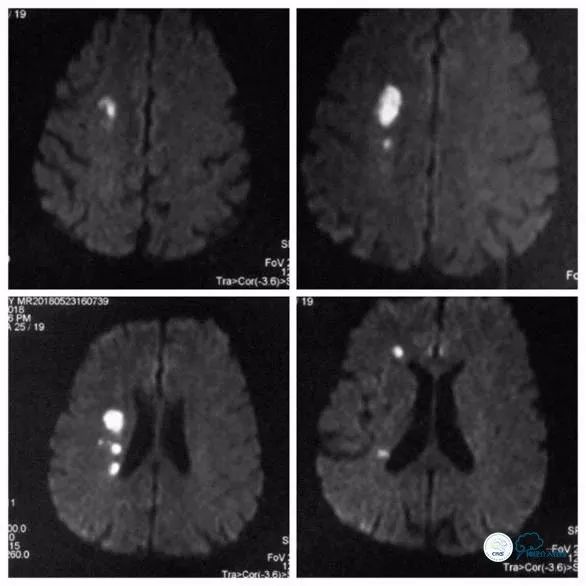

头颅核磁:右前分水岭脑梗死(图1)。

图1